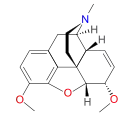

- Isocodeine

Isocodeine Isocodeine |